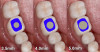

Fig 2. A comparison of several implant diameters to the emergence profile shape of a mandibular molar shows how much emergence in the restoration would be required to replicate the missing tooth.

Figure 2